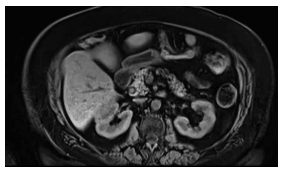

Realizou-se uma ressonância, conforme mostra a imagem a seguir.

Realizou-se uma ressonância, conforme mostra a imagem a seguir.